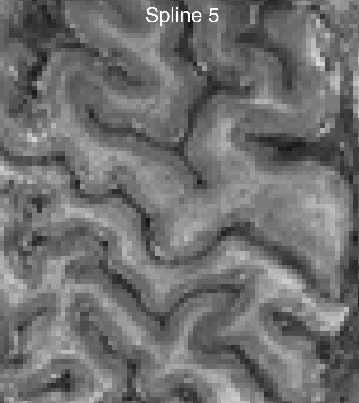

Strategy 4: Using an appropriate spatial interpolation algorithm

The spatial resampling can be done with multiple interpolation algorithms. Most popular might be: Nearest Neighbor, linear, and spline. To my surprise, resampling with a linear interpolation is much to blurry for its popularity.

My personal advise is to refrain from interpolation methods of Nearest-Neighbor or “linear” and use a higher order splines instead.